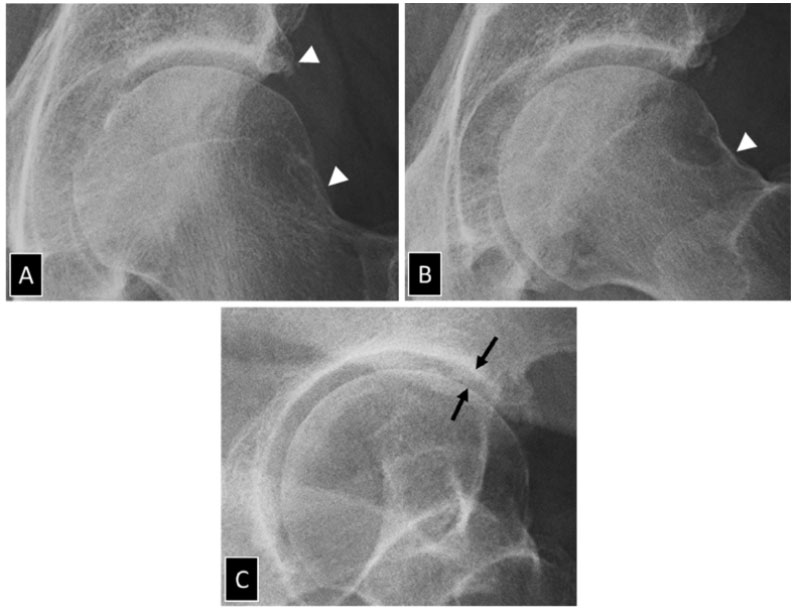

Cấp độ 1 – Nghi ngờ: Khe khớp có dấu hiệu hẹp nhẹ, có thể xuất hiện gai xương nhỏ quanh đầu khớp.

X- quang cho thấy khe khớp hẹp nhẹ ở cả hai bên, xơ cứng xuất hiện dưới sụn tại ổ cối.X-quang AP và Lauenstein bên thể hiện khoảng cách khe khớp, xuất hiện gai xương – Ảnh: Tạp chí điện tử SpringerLink Nature, Hoa Kỳ.

Cấp độ 2 – Nhẹ: Khe khớp hẹp rõ hơn, gai xương dần rõ ràng, xơ cứng tại xương dưới lớp sụn.